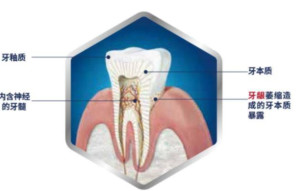

牙齿的牙冠是由牙釉质、牙本质、 牙髓组成。牙釉质位于牙冠表面,是一层坚硬、白色透明的组织,它保护着牙齿内部的牙本质和牙髓组织。因此,光亮完好的牙釉质是牙齿健康的保证。 当我们长期食用含酸性成分高的食物时,牙齿表面牙釉质就会脱钙。 [1]

1、牙釉质受损是一种微观表现,肉眼不易觉察,但是会产生一些继发症,如 牙髓炎、 牙周炎、 牙龈萎缩。调查显示,中国大部分人群患有不同的程度的口腔疾病,均和牙釉质受损后使细菌容易入侵有关。

2、牙釉质受损会导致 牙本质小管暴露,引起 牙本质过敏,俗称 牙齿过敏。当受到冷、热、酸、甜以及机械作用等外界刺激时,使牙齿产生强烈的酸痛感。

3、牙釉质破坏后, 牙本质缺乏有效的保护而直接暴露,容易受到细菌侵蚀,形成 牙菌斑,此时的牙釉质如不及时进行修复,会导致牙齿的永久性损伤--蛀牙。